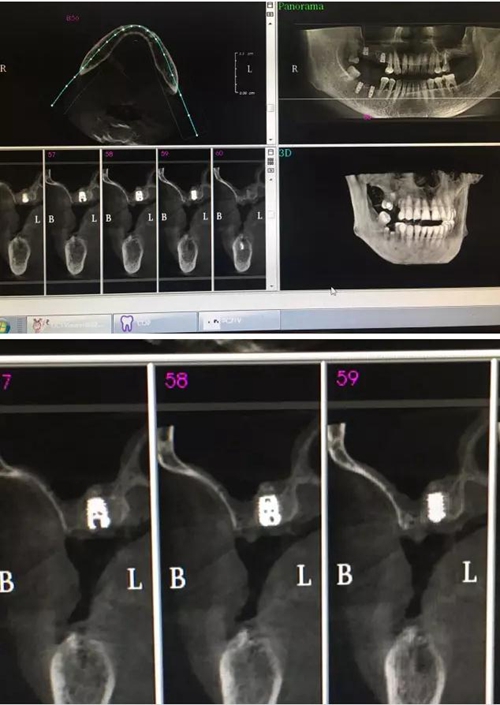

【病例分享】?jī)?nèi)提,用自體骨柱,不用骨粉

2.jpg